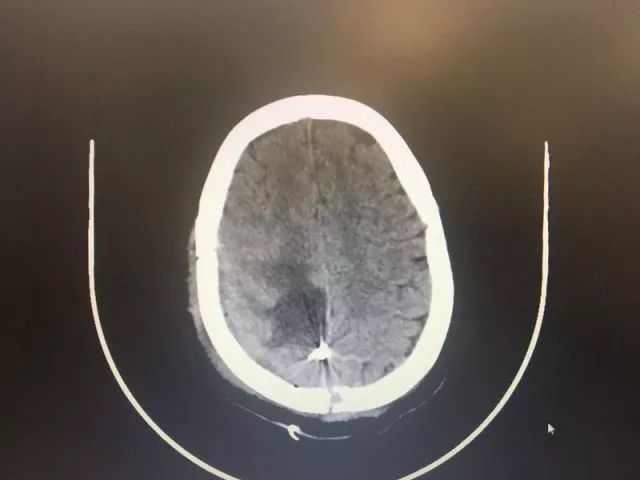

术后复查DSA

血管畸形并血流现相关性动脉瘤全切

5月15日,小鹿被推进了手术室。对于小鹿脑血管畸形团周围"寸土寸金"的脑组织,医生们下刀颇为仔细,尽可能把损伤降到最低,并且对附近非常重要的引流静脉做了妥善保护,还发现并处理了畸形团供血动脉上的动脉瘤,终于,在两个半小时后,一个直径为4公分左右的脑血管畸形团被成功剥离切除。